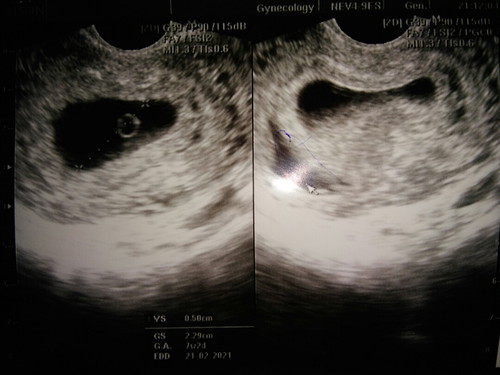

ซาวด์ตอน 8วีคไม่เจอตัวเด็ก เลยซาวด์ผ่านช่องคลอด เจอแต่ถุงไข่ ไม่มีเด็กกับหัวใจ และมีน้ำหรือเลือดอยู่นอกถุงตั้งครรภ์ แบบนี้มีสิทธิ์แท้งไหมค่ะ กังวลมากๆค่ะ ท้องสอง